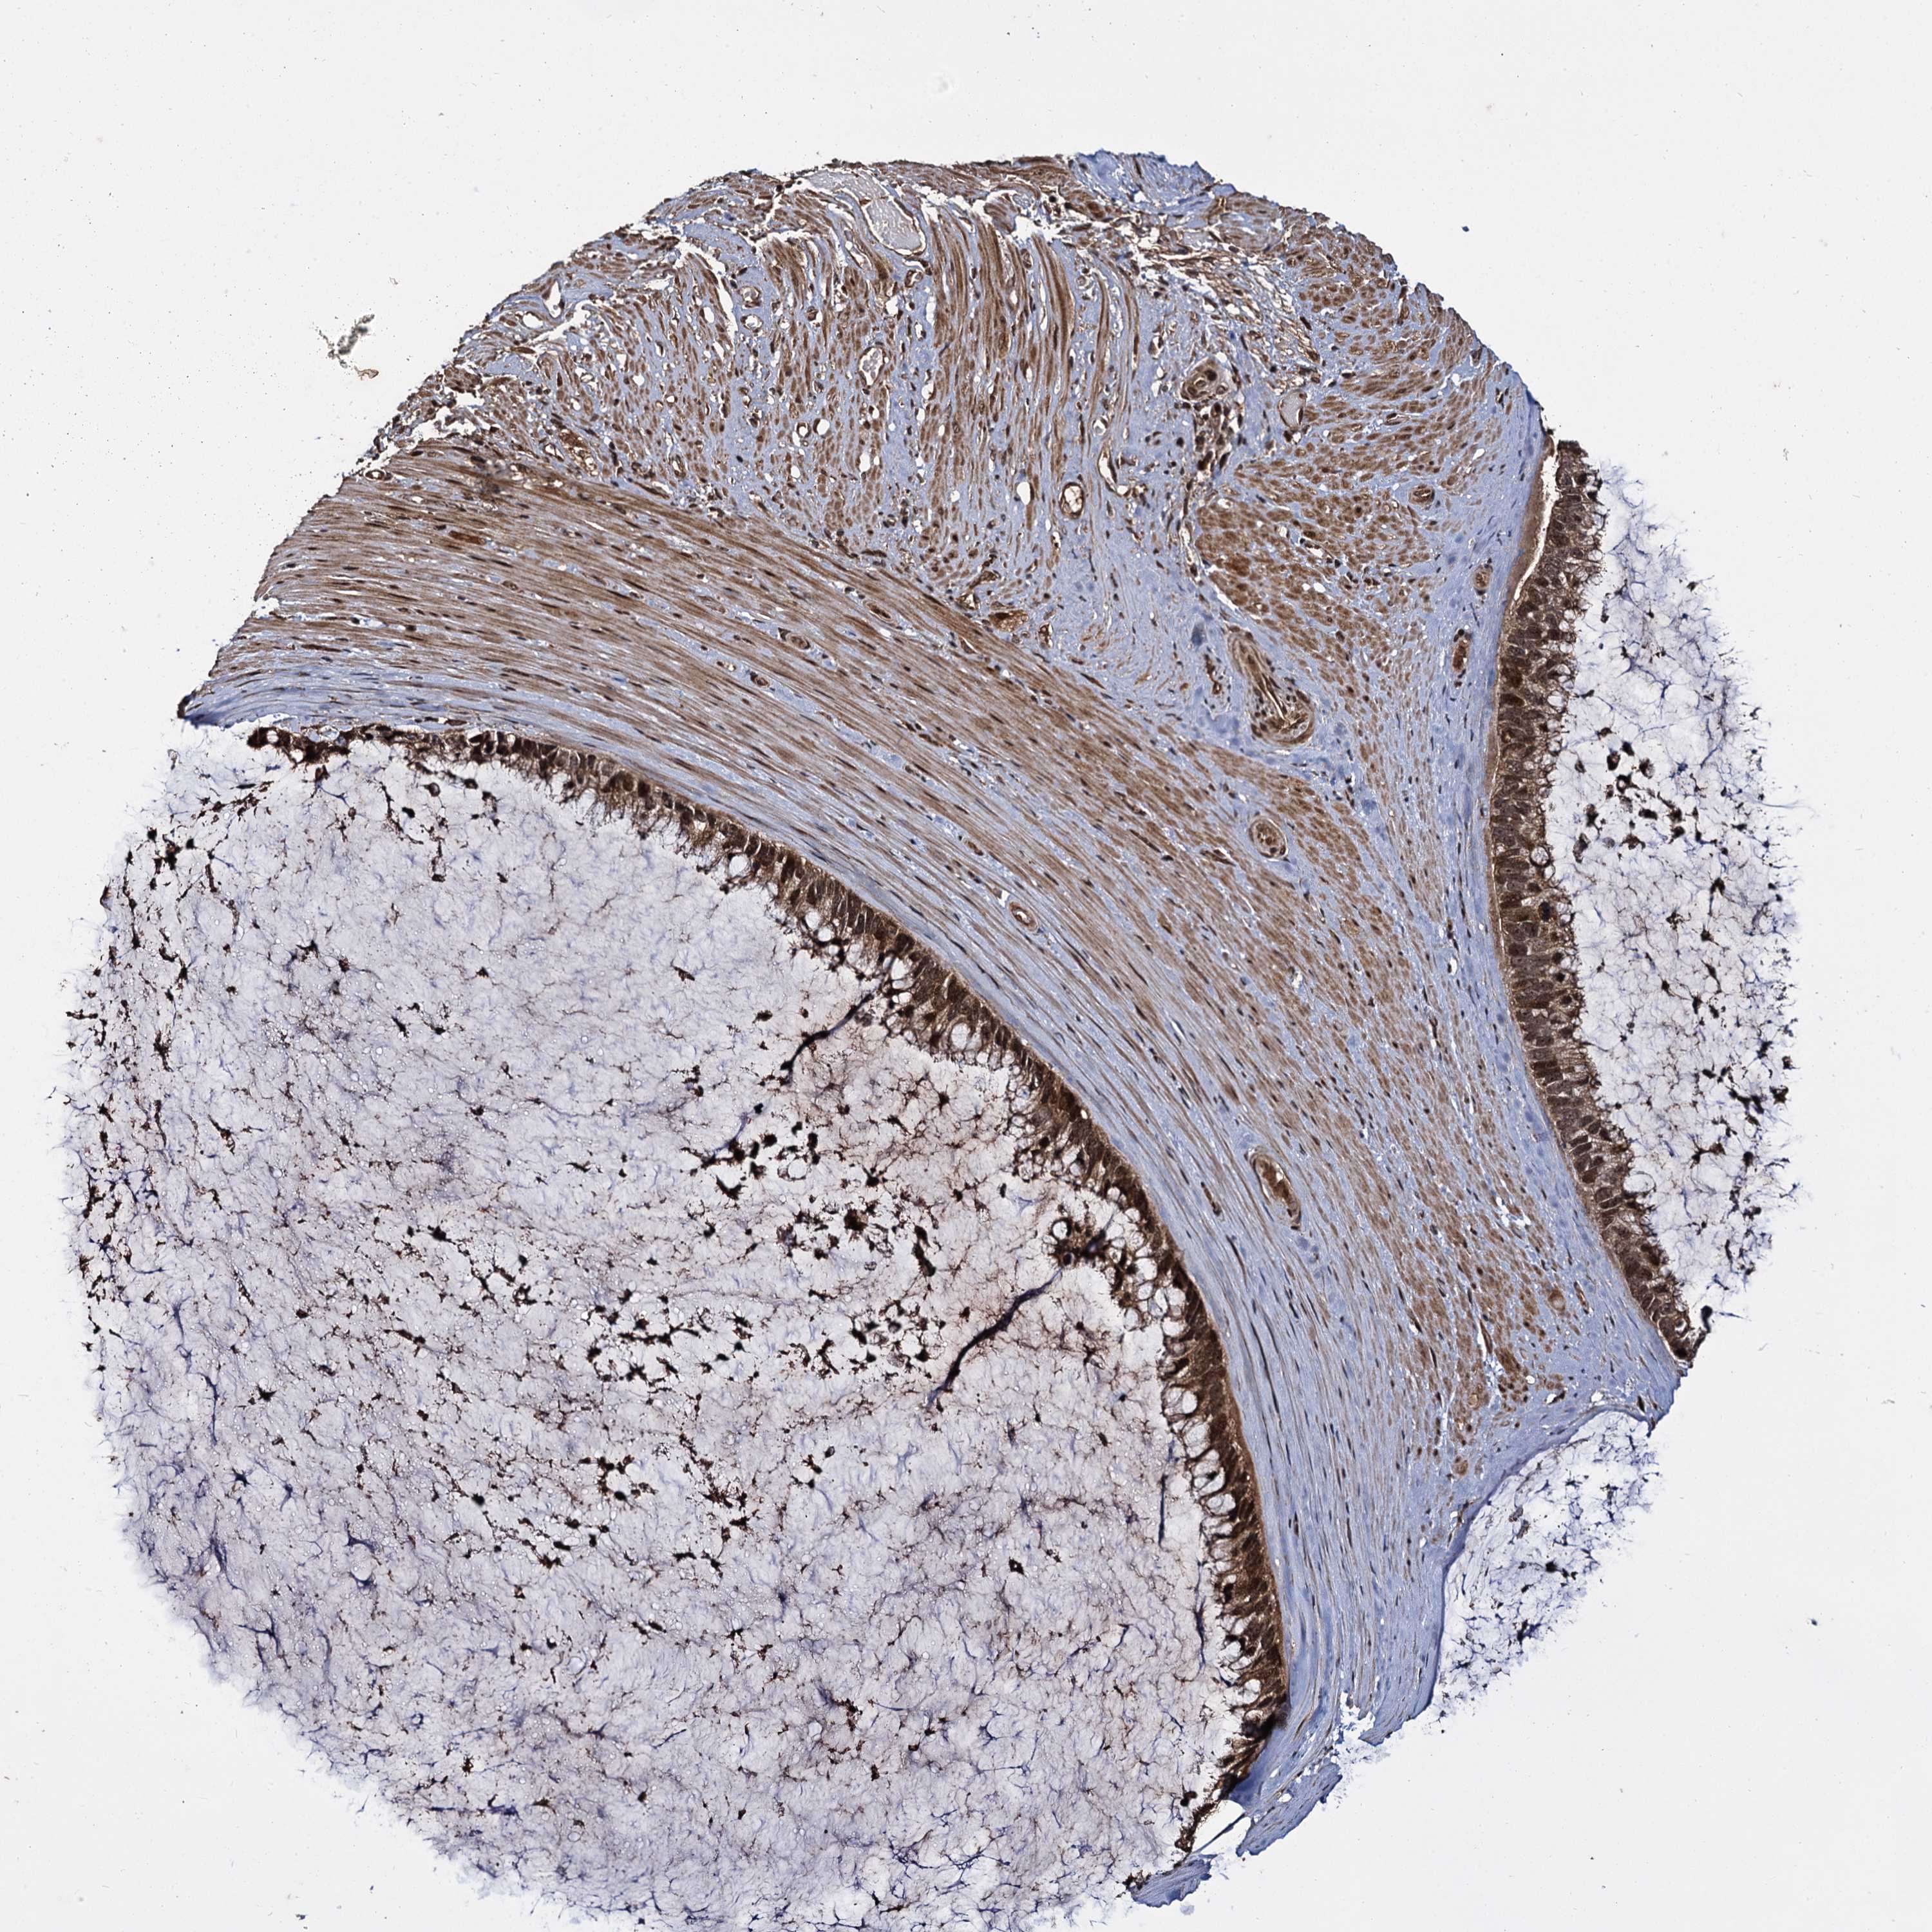

OVARIAN CANCER - Protein expressioni

A mouse-over function shows sample information and annotation data. Click on an image to view it in a full screen mode. Samples can be filtered based on level of antibody staining by selecting one or several of the following categories: high, medium, low and not detected. The assay and annotation is described here.

Note that samples used for immunohistochemistry by the Human Protein Atlas do not correspond to samples in the TCGA dataset.

Antibody stainingi

Antibody staining in the annotated cell types in the current human tissue is reported as not detected, low, medium, or high, based on conventional immunohistochemistry profiling in selected tissues. This score is based on the combination of the staining intensity and fraction of stained cells.

Each image is clickable and will lead to virtual microscopy that enables deeper exploration of all samples and also displays staining intensity scores, fraction scores and subcellular localization as well as patient and tissue information for each sample.

Antibody HPA039392

Antibody HPA040503

Cystadenocarcinoma, serous, NOS

Carcinoma, endometroid

Cystadenocarcinoma, mucinous, NOS

Carcinoma, NOS